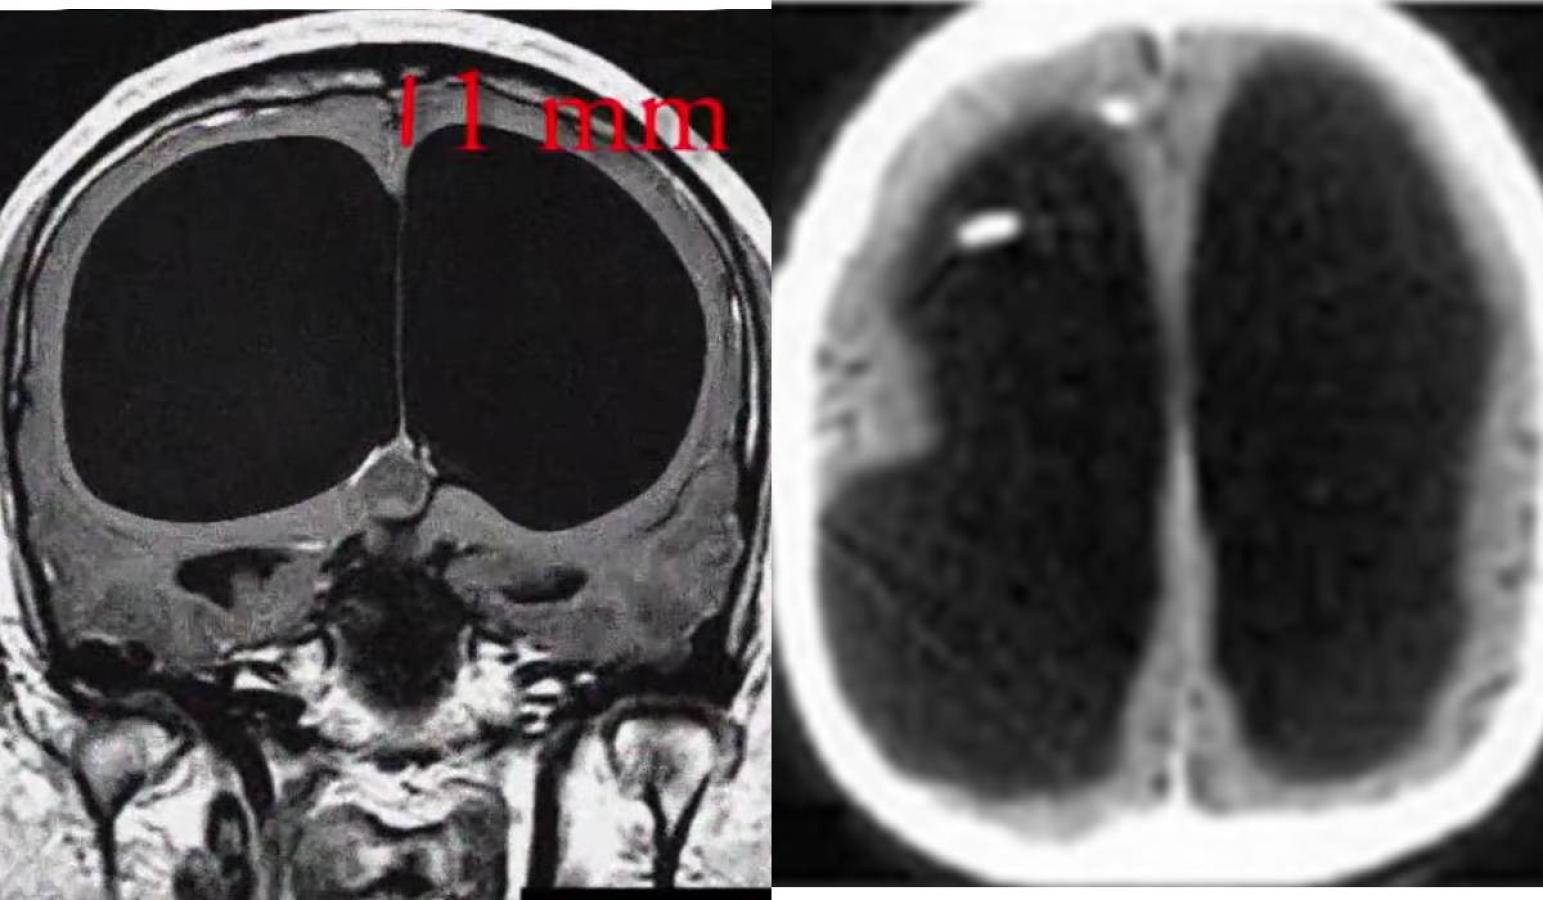

Para disipar sus dudas, decidió realizarle un escáner cerebral. El resultado le voló la cabeza: el muchacho prácticamente no tenía cerebro. Se veía un enorme "hueco" en donde debería estar el cerebro.

Tenía una enfermedad llamada hidrocefalia, en la que “el líquido cerebroespinal no viaja a través del cerebro, sino que habita la cavidad craneal”.

Cabe señalar que no se cuenta con los escáneres realizados por Lorber, y las imágenes mostradas son de otros casos que se han conocido, pero representan el estado del joven.